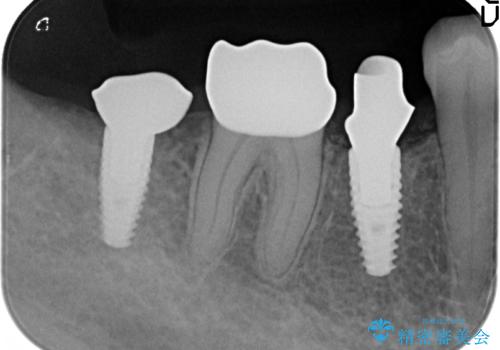

- 右下の奥歯の被せ物が外れてしまったので診て欲しいといらっしゃった方の症例です。

右下7は欠損しており、右下5は保存不可能だったため、インプラントによる欠損補綴を行いました。

インプラント埋入時には骨が不十分な部位に骨増生を行っております。